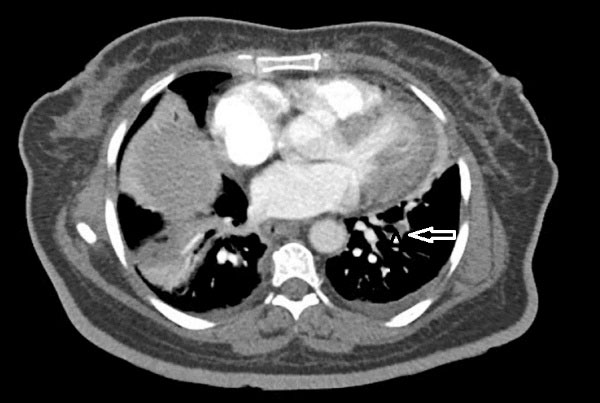

Chest CT revealed scattered nodules in both lungs with several consolidation and peripheral ground glass opacities (halo sign) in both upper and lower lobs of the lung suggestive of septic emboli. In addition, sub segmental collapse consolidation in base of Right Lower Lobe and mild pleural effusion in right side were seen. (Figure 3, Supplementary Files, Video 5, 6).

Figure 3.

Chest CT revealed scattered nodules in both lungs with several consolidations and peripheral ground glass opacity in both upper and lower lobs of lung, suggestive of septic emboli